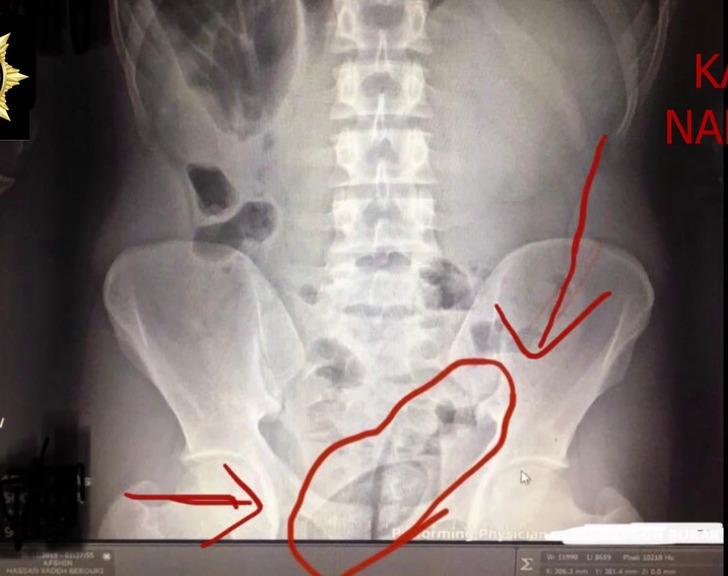

Kars'ta Narkotik Suçlarla Mücadele Şube Müdürlüğü ekiplerinin aldığı ihbar üzerine yaptığı operasyonda karşılaşılan durum 'pes' dedirtti. İran uyruklu iki şüphelinin doktor kontrolünde çekilen röntgenle ilginç bir gerçek gün yüzüne çıktı. Doktorlar tarafından çekilen röntgen sonucunda şüphelilerin bağırsaklarında kapsül içinde 150 gram metamfetamin ve 30 gram kubar esrar taşıdıkları öğrenildi.

GERÇEĞİ RÖNTGEN FİLMİ ORTAYA ÇIKARDI

Hastanede çekilen röntgen filminde, ikilinin bağırsaklarında kapsüller olduğu görüldü. İlaç verilerek doğal yollarla çıkmaları sağlanan kapsüllerde 150 gram metamfetamin ile 30 gram kubar esrar olduğu belirlendi. Narkotik polisi, A.H.Z.B., H.B. ve Türk vatandaşı E.A.'yı 'uyuşturucu ve uyarıcı madde ticareti' suçundan adliyeye sevk etti. 3 şüpheli tutuklanarak cezaevine gönderildi. (DHA)